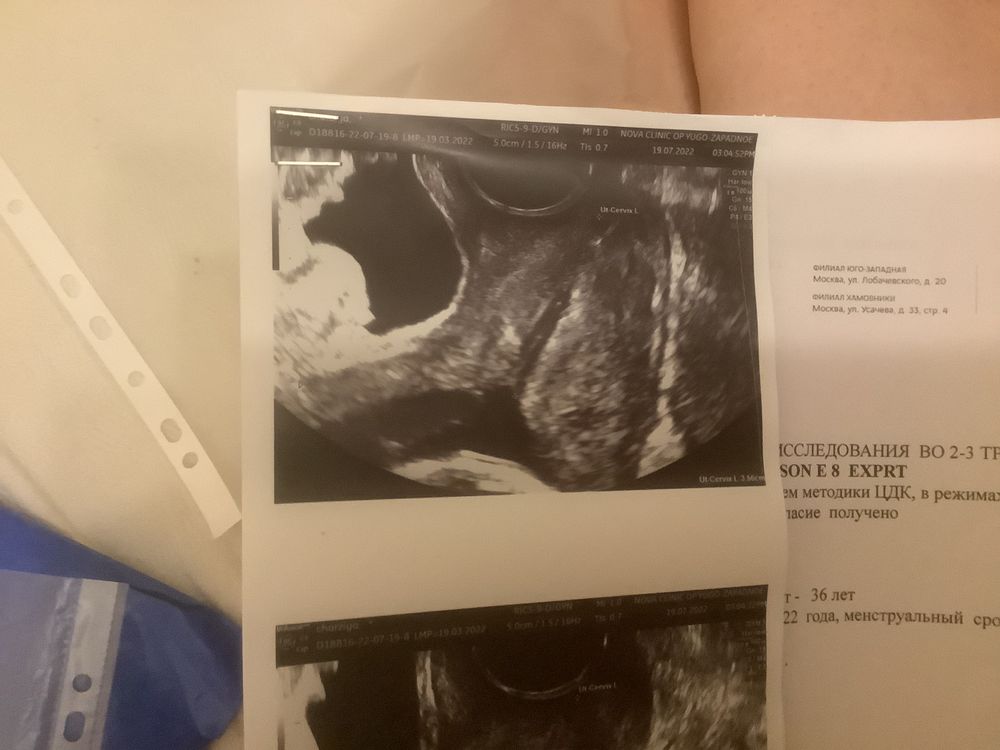

Девочки подскажите, беременность 17 недель,вчера сходил на платное узи смотрели шейку и кровотоки , шейка 32-35 мл , зев закрыт но визуально кажется что открыт так как там слизь. Вообщем все нор.м, как сказала узистка. Но я вчера начиталась как девочки теряют беременность за 10 дней так как шейку не мониторят, и у меня паника началась, теперь я не верю что у мен все нормально. Доктор в жк в отпуске она вообще назначала мне узи шейки 29 июня и теперь только скрининг 1 августа, и сказала что шейка должна быть минимум 35 мм. Кстате я на утрожестане 2 свечи 2 раза в день. Кто разбирается, мне паниковать или нет. ?!подскажите плиз

Я вижу на снимках, что цервикальный канал немного раскрыт, он должен быть сомкнут. Насколько это критично только с врачом